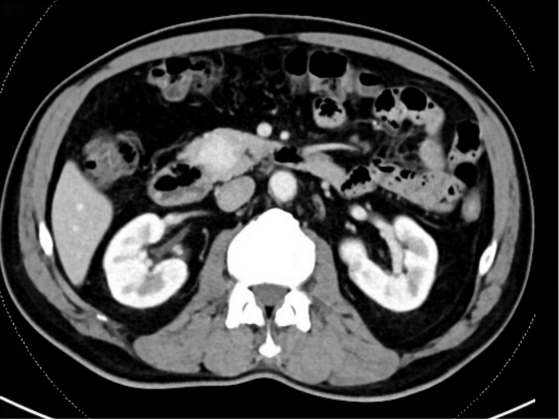

患者杨先生因“上腹部疼痛不适1月余”至扬州大学附属医院肝胆外科副主任、主任医师陶立德团队专家门诊就诊,查腹部CT结果检查结果示“胰头部占位”,予收住入院进一步诊治。入院后完善相关检查,认真评估患者肿瘤情况,考虑为胰腺神经内分泌肿瘤。

该患者肿瘤位于胰头部,治疗难度很大。扬大附院肝胆外科、影像科、麻醉科、消化内科、内分泌科等为其联合施行了多学科联合诊疗(MDT)。经术前精准评估,最终拟定两种手术方案进行比较选择:第一种方案是按传统手术方式施行保留幽门的胰十二指肠切除术,手术需切除十二指肠、部分胆总管、胆囊、胰头等,并完成胃肠、胰肠、胆肠等三处吻合,但该手术存在围手术期并发症多、患者术后会出现消化道功能障碍、营养不良等状况,影响生活质量,通常适用于预期生存期短的恶性肿瘤患者。第二种方案,施行胰头部分切除手术,即仅切除肿瘤及周围胰腺组织,术中完整保留胆管、十二指肠,避免胰管损伤,该方案优点在于在减少术中出血量、缩短手术时间、保护胰腺分泌功能等,预后远期效果优于前者。